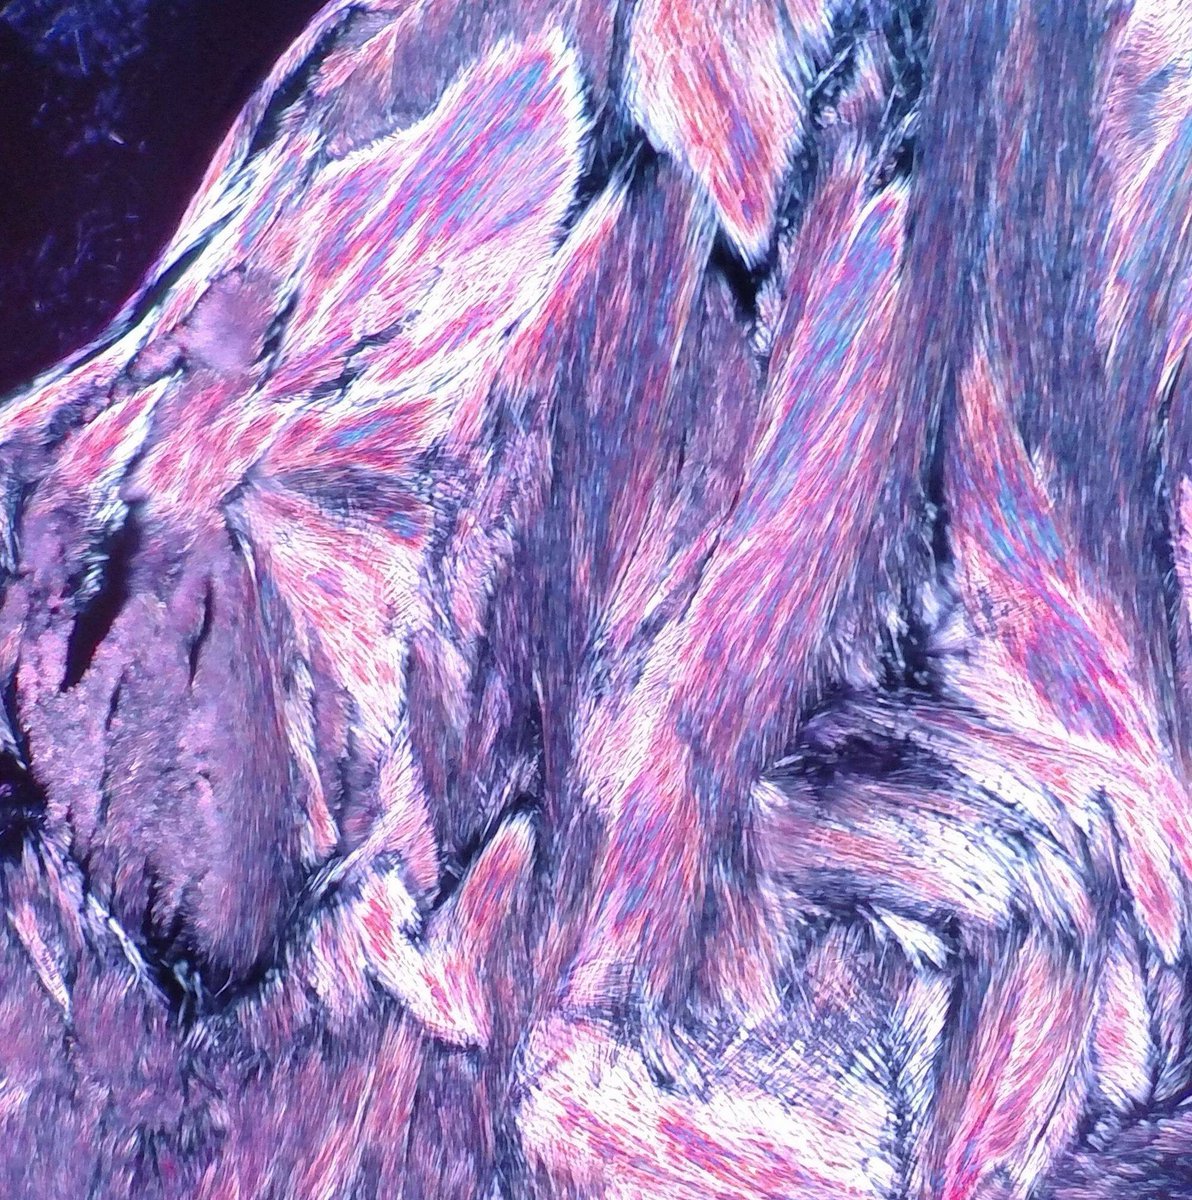

The most beautiful gout picture I have ever seen! From Theresa Smith of #SoMeDocs (lucky picture from a new scope and polarizer on embedded tissue). Ten important facts about gout here: creakyjoints.org/treatment/teng… #pathart The Pathologist Human Pathology